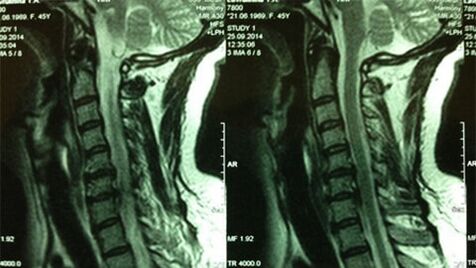

- X -Ray of the department of Cervical;In the initial stage of the process, the magnetic resonance of the department of Cervical will be more informative (it will guarantee the high quality visualization of the solid and soft tissues, it will show the condition of the intervertebral discs, the presence of osteophytes, deformations, damage to the nerve roots and the blood vessels; it will evaluate the condition of the ligaments, muscles, bone tissue;